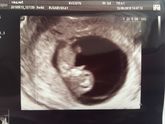

Самое невероятное смотреть через экран на малыша, которого ещё не чувствуешь? итак...Свд 41 мм, ктр 31 мм, соответствует 10,3 неделям☺️плавает там, толкается, так мило? А самое главное - ОТСЛОЙКА ЗАРОСЛА ???ура!!! Сердечко 123 уд/мин, врач сказала хорошо … Читать далее

2 недели назад поставили отслойку 18*5 мм, неделю назад она уменьшилась до 15*5 мм. Добавляла таблетку дюфасто.на и аскорути.н. 6 мая встала на учёт, врач сказала отменить аскорути.н и пить транекса.м. Вчера был первый день приёма его, и в ночь меня … Читать далее

Сходила на узи посмотреть, что там с моей отслойкой) ровно неделя прошла. Отслойка была 18х5 мм, стала 15х5 мм и уплотнилась. Врач сказала возможно и не буду кровить) По остальному соответствуем сроку: свд был 18 мм, стал 28; ктр был 10 мм, стал 15,5 … Читать далее